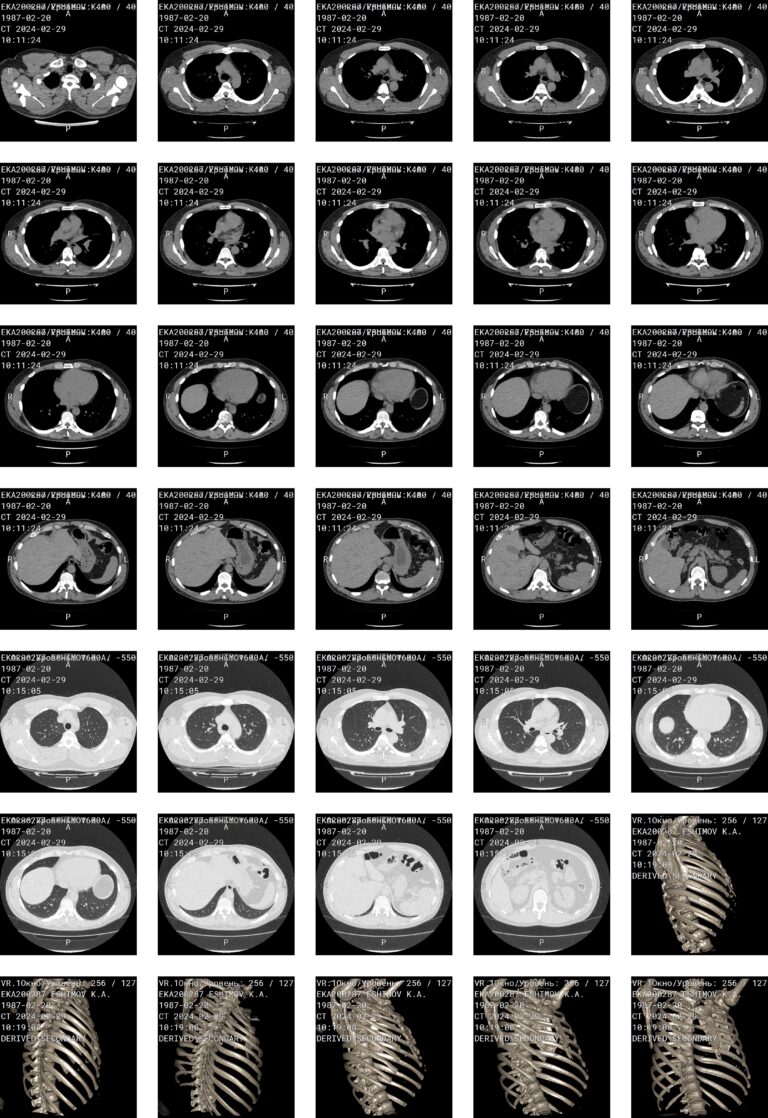

На рентгенограмме живота видны: газовый пузырь желудка, пневматизированные петли кишки, почки, печень, большие поясничные мышцы, диафрагма, нижние ребра, крылья подвздошных костей, боковые отделы брюшной полости. Этот вид диагностики чаще всего позволяет заметить не хроническую, медленно развивающуюся патологию, а экстренные изменения: нахождение жидкости и газа в местах, им несвойственных.

Внимание рентгенолога направлено на то, есть или нет на снимке:

- Свободный газ под куполом диафрагмы;

- Участки скопления газа в кишечнике;

- Горизонтальные уровни жидкости;

- Рентгеноконтрастные конкременты в области почек и желчного пузыря;

- Инородные тела.